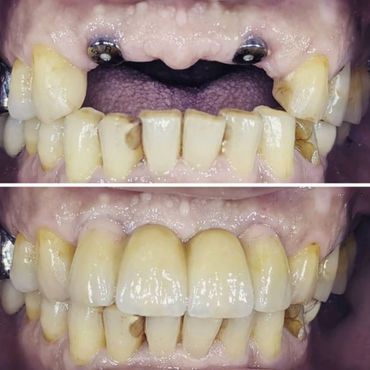

When natural teeth are lost, the face begins to show signs of aging due to bone loss. If you wait too long, the food chewing muscles begin to shorten to accommodate the reduced space between your nose and your chin. Missing one or more teeth could affect the overall health of the surrounding teeth and gums. A dental Implant is the solution to stop bone loss and restore the facial skeletal structure.

A dental implant is an artificial replacement of the root of a tooth. It is a viable option for people of all ages who are in good oral health. The implant is normally a cylinder-shaped metal post inserted and fused into the bone. A replacement tooth is then fitted onto it once it fuses into the bone. With the implant, one can eat, chew, and brush normally.

1. Restore the ability to properly chew and speak.

2. Restore normal facial aesthetics

4. Recover of the natural function of teeth